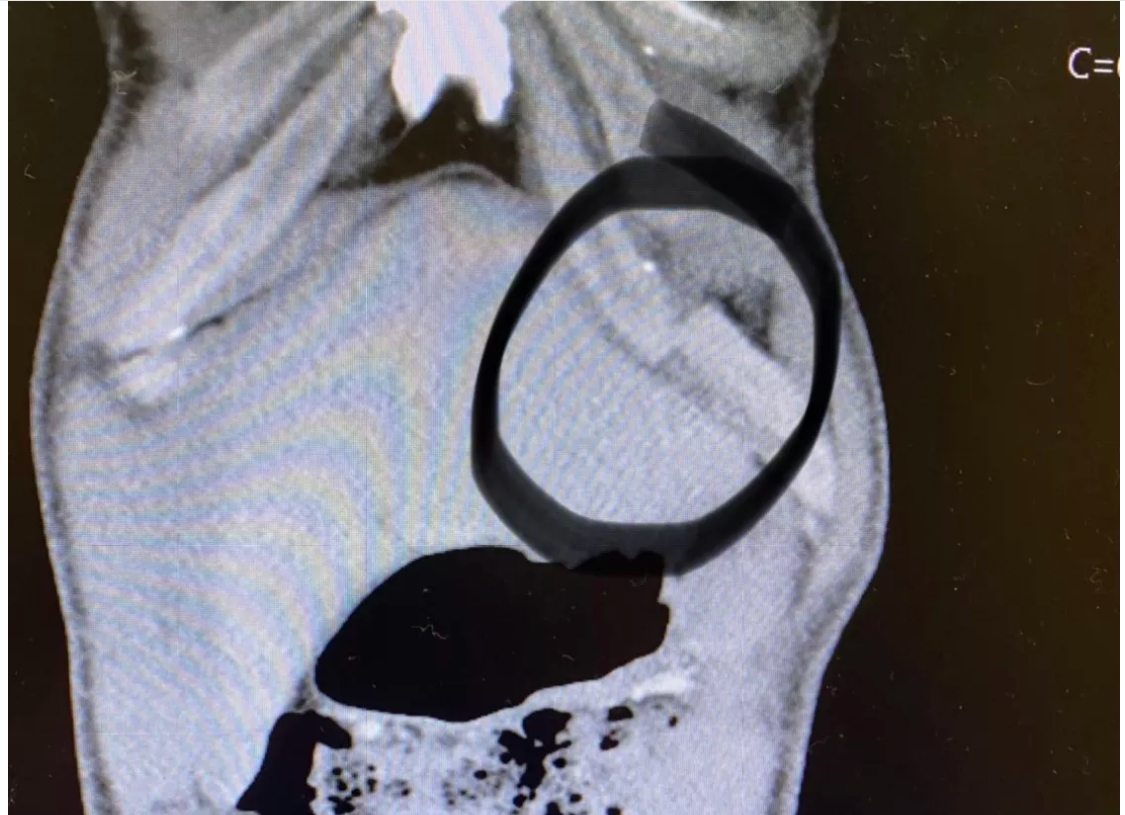

An X-ray of Woodley’s torso, obtained on Sunday by MMA Fighting, appears to show a badly broken rib.

Woodley told ESPN.com he had popped his rib earlier in the fight, and when he attempted to use the guillotine to stand, it popped out again.